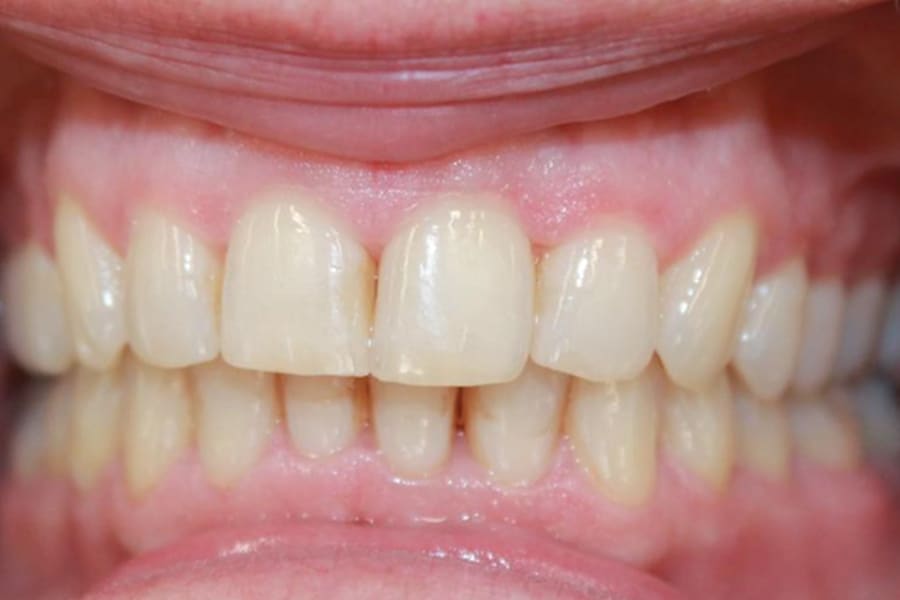

A 54-year-old woman presented with a chief complaint of teeth crowding. After comprehensive digital records were obtained, ClearCorrect® aligner therapy (Straumann, clearcorrect.com) was chosen with an anticipated 12-month treatment duration. The patient exhibited moderate anterior crowding, a class II molar relationship, and narrow arches. The treatment plan aimed to resolve the class II discrepancy, expand the arches, and establish proper anterior alignment. A total of 25 active aligners plus two retention aligners were prescribed. Attachments were selectively placed on the maxillary and mandibular canines to premolars, minimizing bulk while maintaining control over torque and posterior alignment. The patient was instructed to wear class II elastics full-time, which was crucial to achieving molar correction and arch expansion. Her outstanding compliance with class II elastics contributed to a significant improvement in molar position and transverse arch development. After completing the active phase, the patient transitioned to retainers to ensure long-term stability of the results. Given the patient’s initial class II occlusion, monitoring retention was emphasized to prevent relapse. The patient was extremely pleased with the outcome, demonstrating a broadened smile and improved occlusal function. This case underscores the effectiveness of ClearCorrect’s aligners in adult patients, particularly when combined with compliant elastic wear and targeted expansion strategies.

With proper patient compliance, ClearCorrect adult orthodontic therapy can achieve excellent class II correction and esthetic improvement using a non-invasive, aligner-based approach.

ClearCorrect’s aligners have proven effectiveness in adult patients, particularly when combined with compliant elastic wear and targeted expansion strategies.